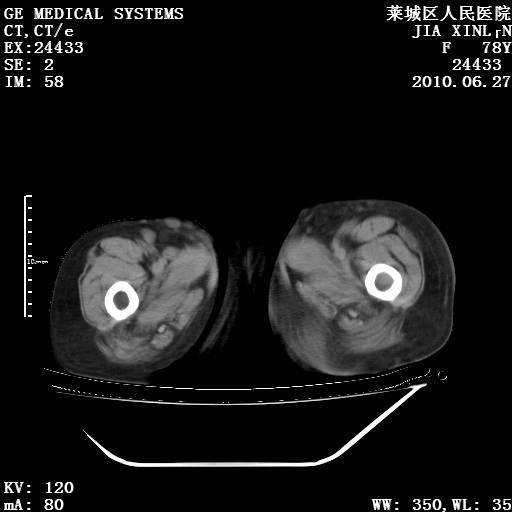

以下是引用胡宇在2010-7-2 19:11:00的发言:[br]神经纤维瘤的特点为:肿块呈多发性、数目不定,少的几个,多的可成百上千难以计数。小的如米粒,大的似拳头,甚至可达十数公斤以上。可松弛地悬挂于皮表,皱褶及松弛可致畸形明显。神经纤维瘤沿神经干的走向生长时呈念珠状,或蚯蚓块状形结节。此外神经纤维瘤皮肤可出现咖啡斑,大小不一,形如雀斑小点状,或大片状,分布与神经纤维瘤肿块的分布无关。肿瘤数目不多的患者,皮肤色素咖啡斑状沉着是纤维神经瘤的重要诊断之一。 本病多发于躯干,有时出现于四肢及面部,患者常合并许多疾病应予重视加以区别。 [br] [br] [br] [br]lyb999说 [br]